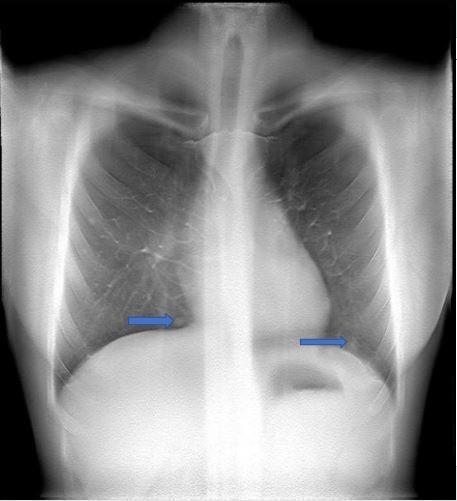

病史: 女 58岁 肝癌肺内转移 采集参数: 定位像: 110KV 0.92mAs 容积参数:110KV 0.25mAs 曝光次数 60 扫描角度 30度 重建起始高度 30mm 终止高度 200mm 层间距 5mm 层数 35 采样因子 1 胸部正位片

影像描述: X线平片:左肺内上叶、下叶见结节样密度增高影 容积图像:双肺见多个大小不等结节样密度增高影 影像诊断:肝癌肺内转移 病例点评: 容积断层图像显示双肺多发结节,较常规X平片所见病灶明显增多。相对于传统胸部X线平片,断层容积图像可以检出更多的肺转移病灶,为治疗方案的制定提供更多的影像学信息。